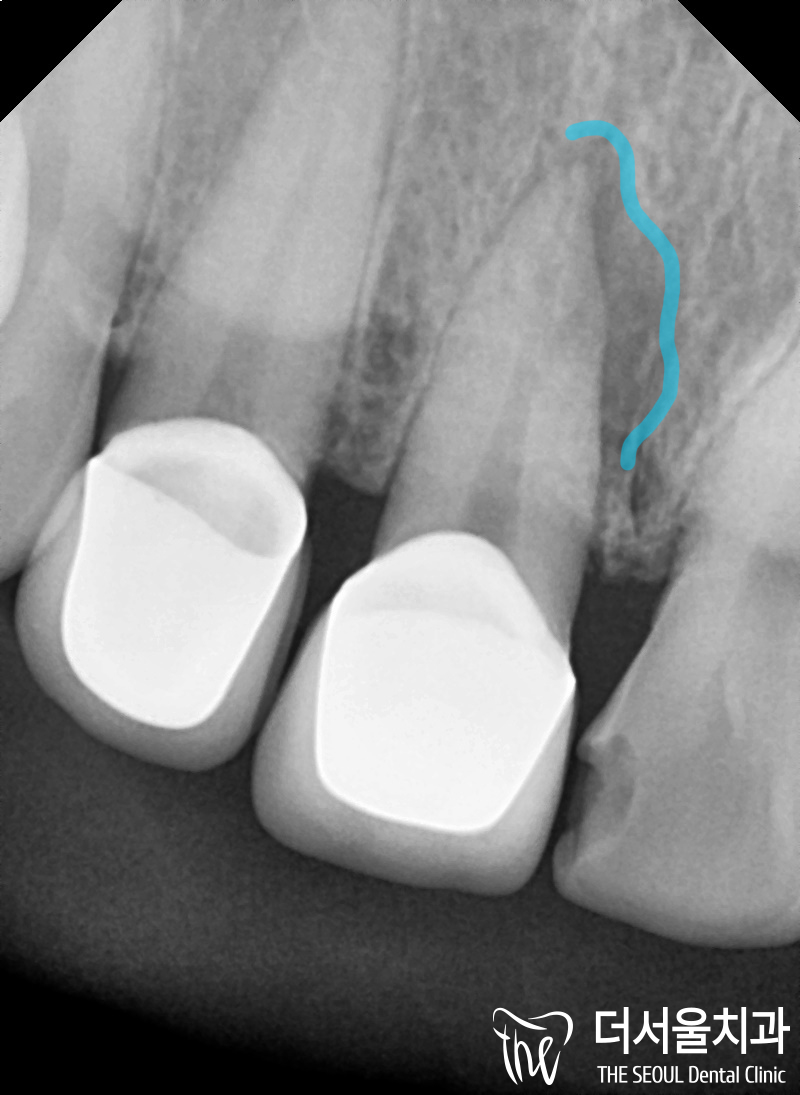

먼저 정면 사진을 보여드립니다.

왼쪽 앞니 2개는 크라운이 씌워져 있고

오른쪽 큰 앞니는 인접면 우식증이

발생 된 것을 볼 수 있습니다.

『그러면서 큰 앞니 사이에는

살짝 틈이 있는것이 보여지죠?』

우선, 통증의 원인을 정확히 찾아야 되서

해상도 높은 엑스레이로 해당 부위의

촬영을 진행했고

그 결과, 일부 염증이 있는 것을

볼 수 있습니다.

파란색으로 표시를 해두었죠?

조금 더 늦게 오셨더라면

앞니를 발치해야 되는

상황까지 발전 되었을 수 있습니다.